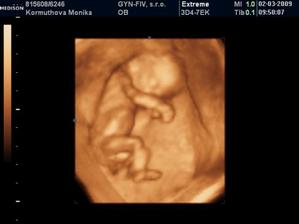

Naše 3D